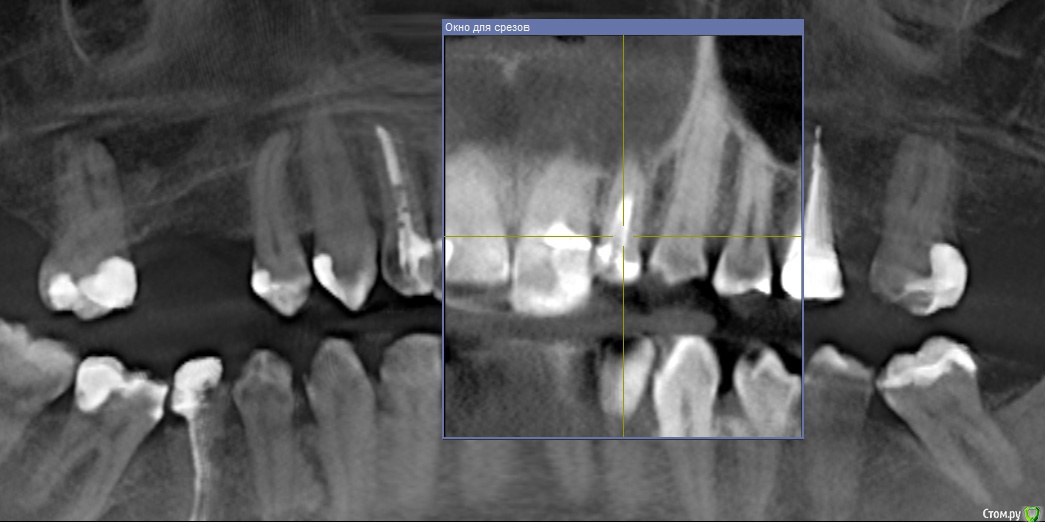

Ankazabolevshaya Опубликовано 28 мая, 2016 Поделиться Опубликовано 28 мая, 2016 Здравствуйте, уважаемые врачи! Очень сильно нуждаюсь в вашей помощи. В 2013 мне лечили два передних зуба (клык и передний). Пломбировали каналы, но коронки не ставили. Этой зимой я почувствовала боль в передних зубах в районе челюсти. Раздражение в дёснах. Резь. Потом вылез какой-то пупырь на десне. Я думала, что это стоматит. Не верила тем, кто мне говорил про нужность обзорного снимка. Признаю свою глупость. Теперь, после КТ оказалось что у меня сломаны эти каналы, а под левым клыком пустота. А пупырь, как мне сказали - это выход свища.Мне предложили зуб удалять. Как-то восстанавливать эту пустоту. Потом делать имплантацию. Есть ли сегодня технологии, позволяющие восстанавливать это пространство под зубом без его удаления, с последующей коронкой на него? И ещё один вопрос: могло ли все это случится из-за какой-нибудь заразы, занесенной во время лечения этих двух зубов в 2013г. ? Так же был момент ранения слизистой левой ноздри, как раз над свищем, который на десне. Просто очень часто слизистая иссыхала в одном месте и я травмировала слизистую. Буду очень благодарна за ответ. От меня в клинике ждут решения, а я переживаю, что улыбка испортится с искусственным зубом. Зуб этот свой очень люблю. Анна. Ссылка на комментарий

red_butler Опубликовано 28 мая, 2016 Поделиться Опубликовано 28 мая, 2016 Спасибо! Можете пояснить, Вы думаете, что зуб можно спасти? если судить только по снимкам, то да 1 Ссылка на комментарий

Ankazabolevshaya Опубликовано 28 мая, 2016 Автор Поделиться Опубликовано 28 мая, 2016 если судить только по снимкам, то даа скажите, как по Вашему, это киста прикорневая? Или челюсть разрушена? Нужно восстановление челюсти? Ссылка на комментарий

Ankazabolevshaya Опубликовано 28 мая, 2016 Автор Поделиться Опубликовано 28 мая, 2016 если судить только по снимкам, то даи корень ведь сломан, поставить под коронки всё равно можно? Ссылка на комментарий

red_butler Опубликовано 29 мая, 2016 Поделиться Опубликовано 29 мая, 2016 а скажите, как по Вашему, это киста прикорневая? Или челюсть разрушена? Нужно восстановление челюсти? это не важно и корень ведь сломан, поставить под коронки всё равно можно? перелома не увидел И еще последнее, как Вы относитесь к процедуре - депофорез? В моём случае стоит в эту торону смотреть? бесполезно 2 Ссылка на комментарий

red_butler Опубликовано 29 мая, 2016 Поделиться Опубликовано 29 мая, 2016 Как же доказать им что нет на самом деле этого перелома (или корневого канала)? Мы видим только часть срезов Кт, а доктора на очном осмотре и ситуацию в полости рта.Сходите еще на пару консультаций. Как по-вашему – скорее всего виноват тот врач (как раз это тот врач, который настаивает на удалении и на переломе канала), который пломбировал каналы этого зуба в 2013? Или я? Сколько по времени такая штука на корне в среднем формируется? Было и ранение слизистой носа было так же ранение десны во время читки нитью, глубокое и долго заживало. Теперь уже не разобраться, виноват ли врач? Вы не правильно понимаете цели форума, Мы отвечаем на вопросы "что делать" Да и раз депофорез бесполезен, то что с Вашей точки зрения предпочтительнее сегодня в моём случае? Лазер или иссечение корня? Повторное лечение корневого канала. 3 Ссылка на комментарий